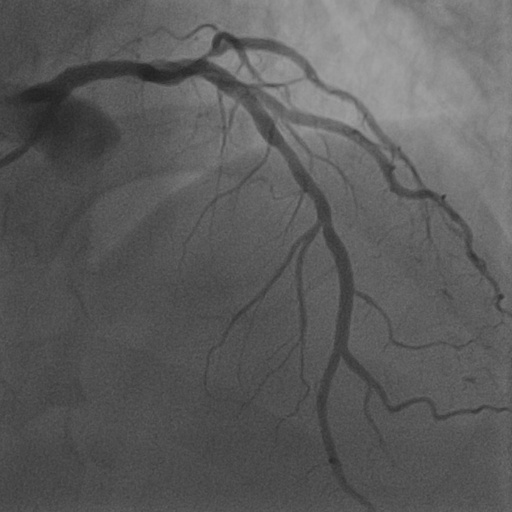

4.1 XACV Dataset

We collect 111 complete records of coronary artery X-ray videos from 59 patients, encompassing the injection, flow through the blood vessels around the heart, and dissipation of the contrast agent. Subsequently, we establish the XACV (X-ray Angiography Coronary Video) dataset. Each video consists of an average of 86 frames of high-resolution coronary artery X-ray images, with an equal distribution of left and right coronary arteries. We invite experienced radiologists to annotate the vascular regions, focusing on one or two frames where the contrast agent is most prominent in each video. These annotations are used only for evaluation in our method, not for training, maintaining the unsupervised nature of our approach. The data collection protocol involves several key steps, including patient preparation with informed consent and metal object removal, image capture using a Philips Allura Xper FD20 machine for standardized frontal (PA) and lateral views, DICOM file storage, and de-identification for patient privacy. Experienced radiologists perform diagnostic annotations using standardized tools and methods, with multiple annotations to enhance accuracy. Quality control measures, secure data management, and strict adherence to ethical guidelines and privacy regulations are implemented throughout the process. The XCAD dataset contains only a single image, and the CADICA video dataset does not provide corresponding ground truth. Therefore, in the following experiments, we conduct all the analyses on our collected XACV dataset and the corresponding GT for each sequence. In Figure 5, we show that compared to other publicly available datasets, XCAD (Ma et al., 2021) and CADICA (Jiménez-Partinen et al., 2024), our dataset exhibits finer annotations in the vascular regions, providing an advantage for future related tasks. The development and use of our dataset have been approved by our institution’s IRB. We will make the XACV dataset publicly available.